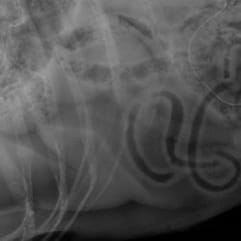

german shepherd x-ray german shepherd x-ray

Olivia quickly got home and went to the vet with her dog. He had an X-ray so the vet could understand the situation. Imagine everyone's surprise when they discovered the string of lights in the dog's stomach, which he'd eaten the lot! Or rather swallowed.